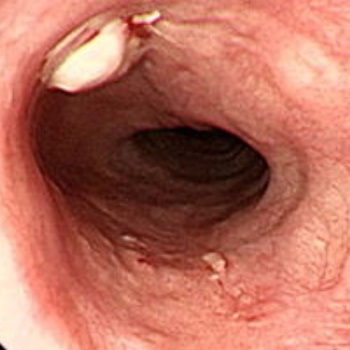

1. 식도암의 초기증상 및 증상

식도암의 초기 증상은 거의 자각하지 못할 수 있으며, 평소 건강진단 과정에서 발견되는 경우가 많습니다.

식도암은 어느 정도 진행되면 본인이 자각할 수 있는 증상으로, 가슴과 허리통증, 체중 감소, 기침, 목소리 잠김 현상 등이 있습니다.

또한 암이 종양이 커지면 식도 안쪽이 좁아져서 음식물을 넘기는 것이 불편해질 수 있습니다.